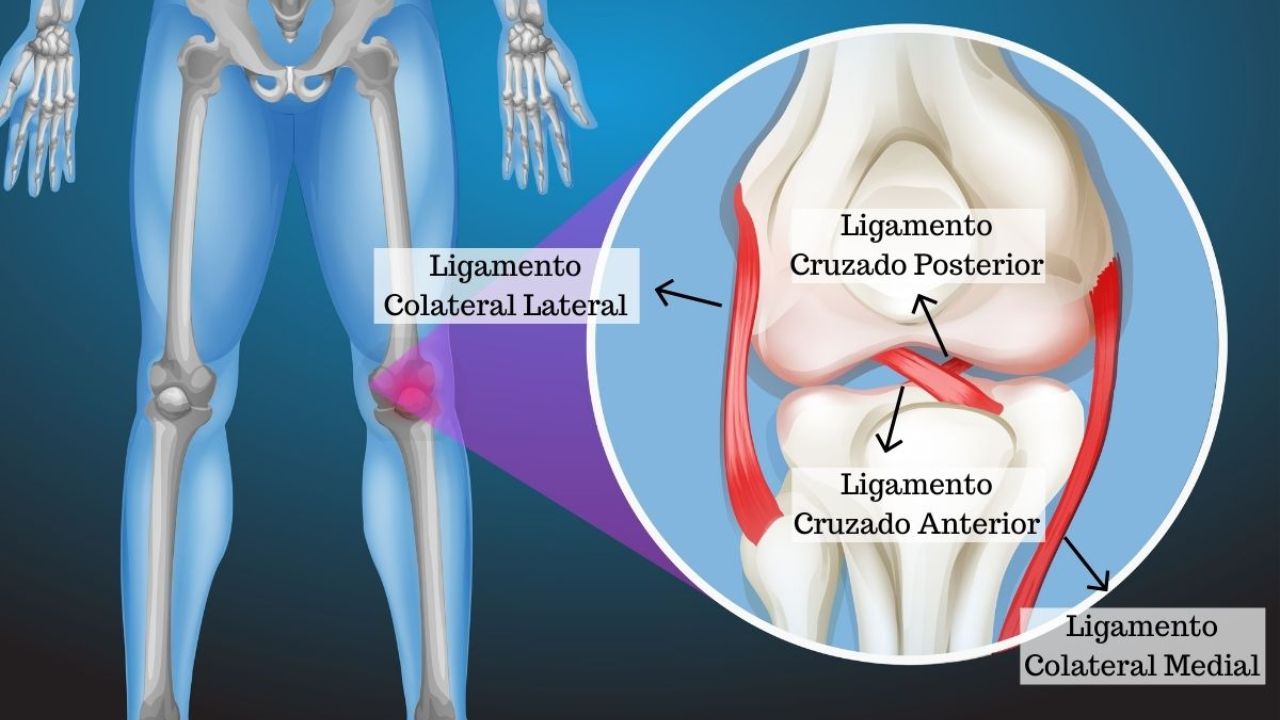

Lesão de LCA Agendar consulta O Ligamento Cruzado Anterior (LCA) é uma das estruturas mais importantes para a estabilidade do joelho. Localizado no centro da

Lesão de LCA Agendar consulta O Ligamento Cruzado Anterior (LCA) é uma das estruturas mais importantes para a estabilidade do joelho. Localizado no centro da